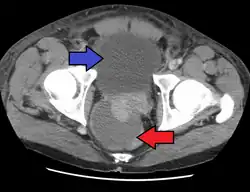

| CT scan showing an abscess of the prostate (red arrow) resulting in urinary retention (blue arrow) | |

The diagnosis should be suspected in someone who has acute prostatitis that is not improving and can be confirmed by medical imaging.[1] The preferred method of imaging is generally ultrasound of the prostate via the rectum.[1] CT scan of the abdomen and pelvis may be less painful.[1] MRI may also be useful in certain cases.[1]